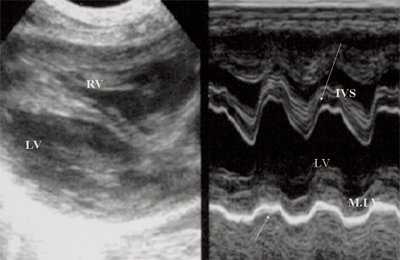

При эхокардиографии изучались четырехкамерный срез сердца плода (рис. 1) и срез через три сосуда (рис. 2). УЗИ проводилось трансабдоминальным датчиком, лишь при необходимости (затрудненная визуализация) использовался внутриполостной датчик. Четырехкамерный срез сердца плода при ультразвуковом сканировании трансабдоминальным датчиком визуализировался в 85% случаев, срез через сосуды - в 73%, при использовании трансвагинального датчика эти цифры существенно возрастали до 100 и 91% соответственно. Оптимизация пренатальной диагностики ВПС может быть достигнута путем строгого соблюдения основных методических правил. При оценке четырехкамерного среза плода необходимо оценить нормальное расположение сердца плода, исключив его эктопию (рис. 3), положение оси сердца плода, что не представляет никаких трудностей, нормальные пропорции и размеры камер сердца, движение створок атриовентрикулярных клапанов должно быть свободным, септальная створка трикуспидального клапана должна располагаться ближе к верхушке сердца (рис. 4). При оценке среза через три сосуда необходимо оценить взаиморасположение сосудов и их диаметр.

Рис. 1. Беременность 12 недель. Четырехкамерный срез сердца плода. Отчетливо видны камеры сердца.

Нагрузка сопротивлением возникает при ситуации, когда выброс крови из желудочков сердца в магистральные сосуды затруднен на уровне полулунных клапанов (стеноз аорты и легочной артерии), подклапанного пространства (идиопатический гипертрофический субаортальный стеноз, подклапанный стеноз аорты или легочной артерии), на протяжении сосудистого русла (коарктация аорты) либо при значительном увеличении выходного сопротивления (синдром Эйзенменгера). В результате затруднения выброса крови резко возрастает напряжение миокарда соответствующего желудочка при относительно стабильном объеме крови, что служит проявлением систолической перегрузки сердца. При систолической перегрузке желудочков сердца независимо от нозологической формы порока полость желудочка, несущего основную нагрузку сопротивлением, умеренно увеличивается в размерах. В ответ на нагрузку сопротивлением на эхокардиограмме выявляется гипертрофия миокарда соответствующего желудочка, и чем больше сопротивление выбросу, тем резче выражена степень гипертрофии миокарда соответствующего желудочка и межжелудочковой перегородки (рис. 1) [3].

Рис. 1. Систолическая перегрузка правого желудочка. Поперечное сечение желудочков сердца при стенозе легочной артерии. Градиент давления правый желудочек - легочная артерия равен 200 мм рт.ст. Выраженная гипертрофия межжелудочковой перегородки и миокарда передней стенки правого желудочка.

Характерными особенностями выраженной объемной перегрузки правого желудочка являются дилатация желудочка, при которой толщина миокарда не превышает верхней границы нормы, увеличение правого предсердия, парадоксальный характер движения межжелудочковой перегородки и увеличение амплитуды движения трикуспидального клапана (рис. 2, 3).

Рис. 2. Длинная ось сердца. Объемная перегрузка правого желудочка при дефекте межпредсердной перегородки. Объем сброса крови превышает 200% МОС. Отмечается выраженная дилатация правого желудочка.

Рис. 3. Объемная перегрузка правого желудочка при дефекте межпредсердной перегородки. В- и М-сканирование. Стрелкой показан парадоксальный характер движения межжелудочковой перегородки.

Для левого желудочка признаком объемной перегрузки являются увеличение полости левого предсердия и желудочка, а также экскурсии межжелудочковой перегородки и миокарда задней стенки левого желудочка (рис. 4).

Рис. 4. Объемная перегрузка левых отделов сердца. В- и М-сканирование. Отмечается усиление экскурсии межжелудочковой перегородки и миокарда задней стенки левого желудочка.

IVS - межжелудочковая перегородка, MLV - миокард левого желудочка, LV и RV - левый и правый желудочек.